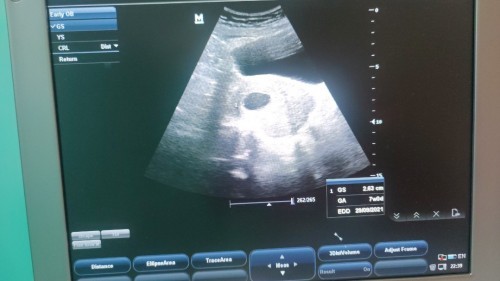

Kantung kosong tanpa kandungan

Ada tak ibu2 yg mengalami situasi yg sama mcm saya.. klu ikut kitaran haid kandungan dh 12m3h tpi bila scan doc ckp kantung kosong tanpa kandungan dan saiz cuma 7minggu.. saiz kantung membesar tapi tk nampak isi & tkde degupan jantung baby...